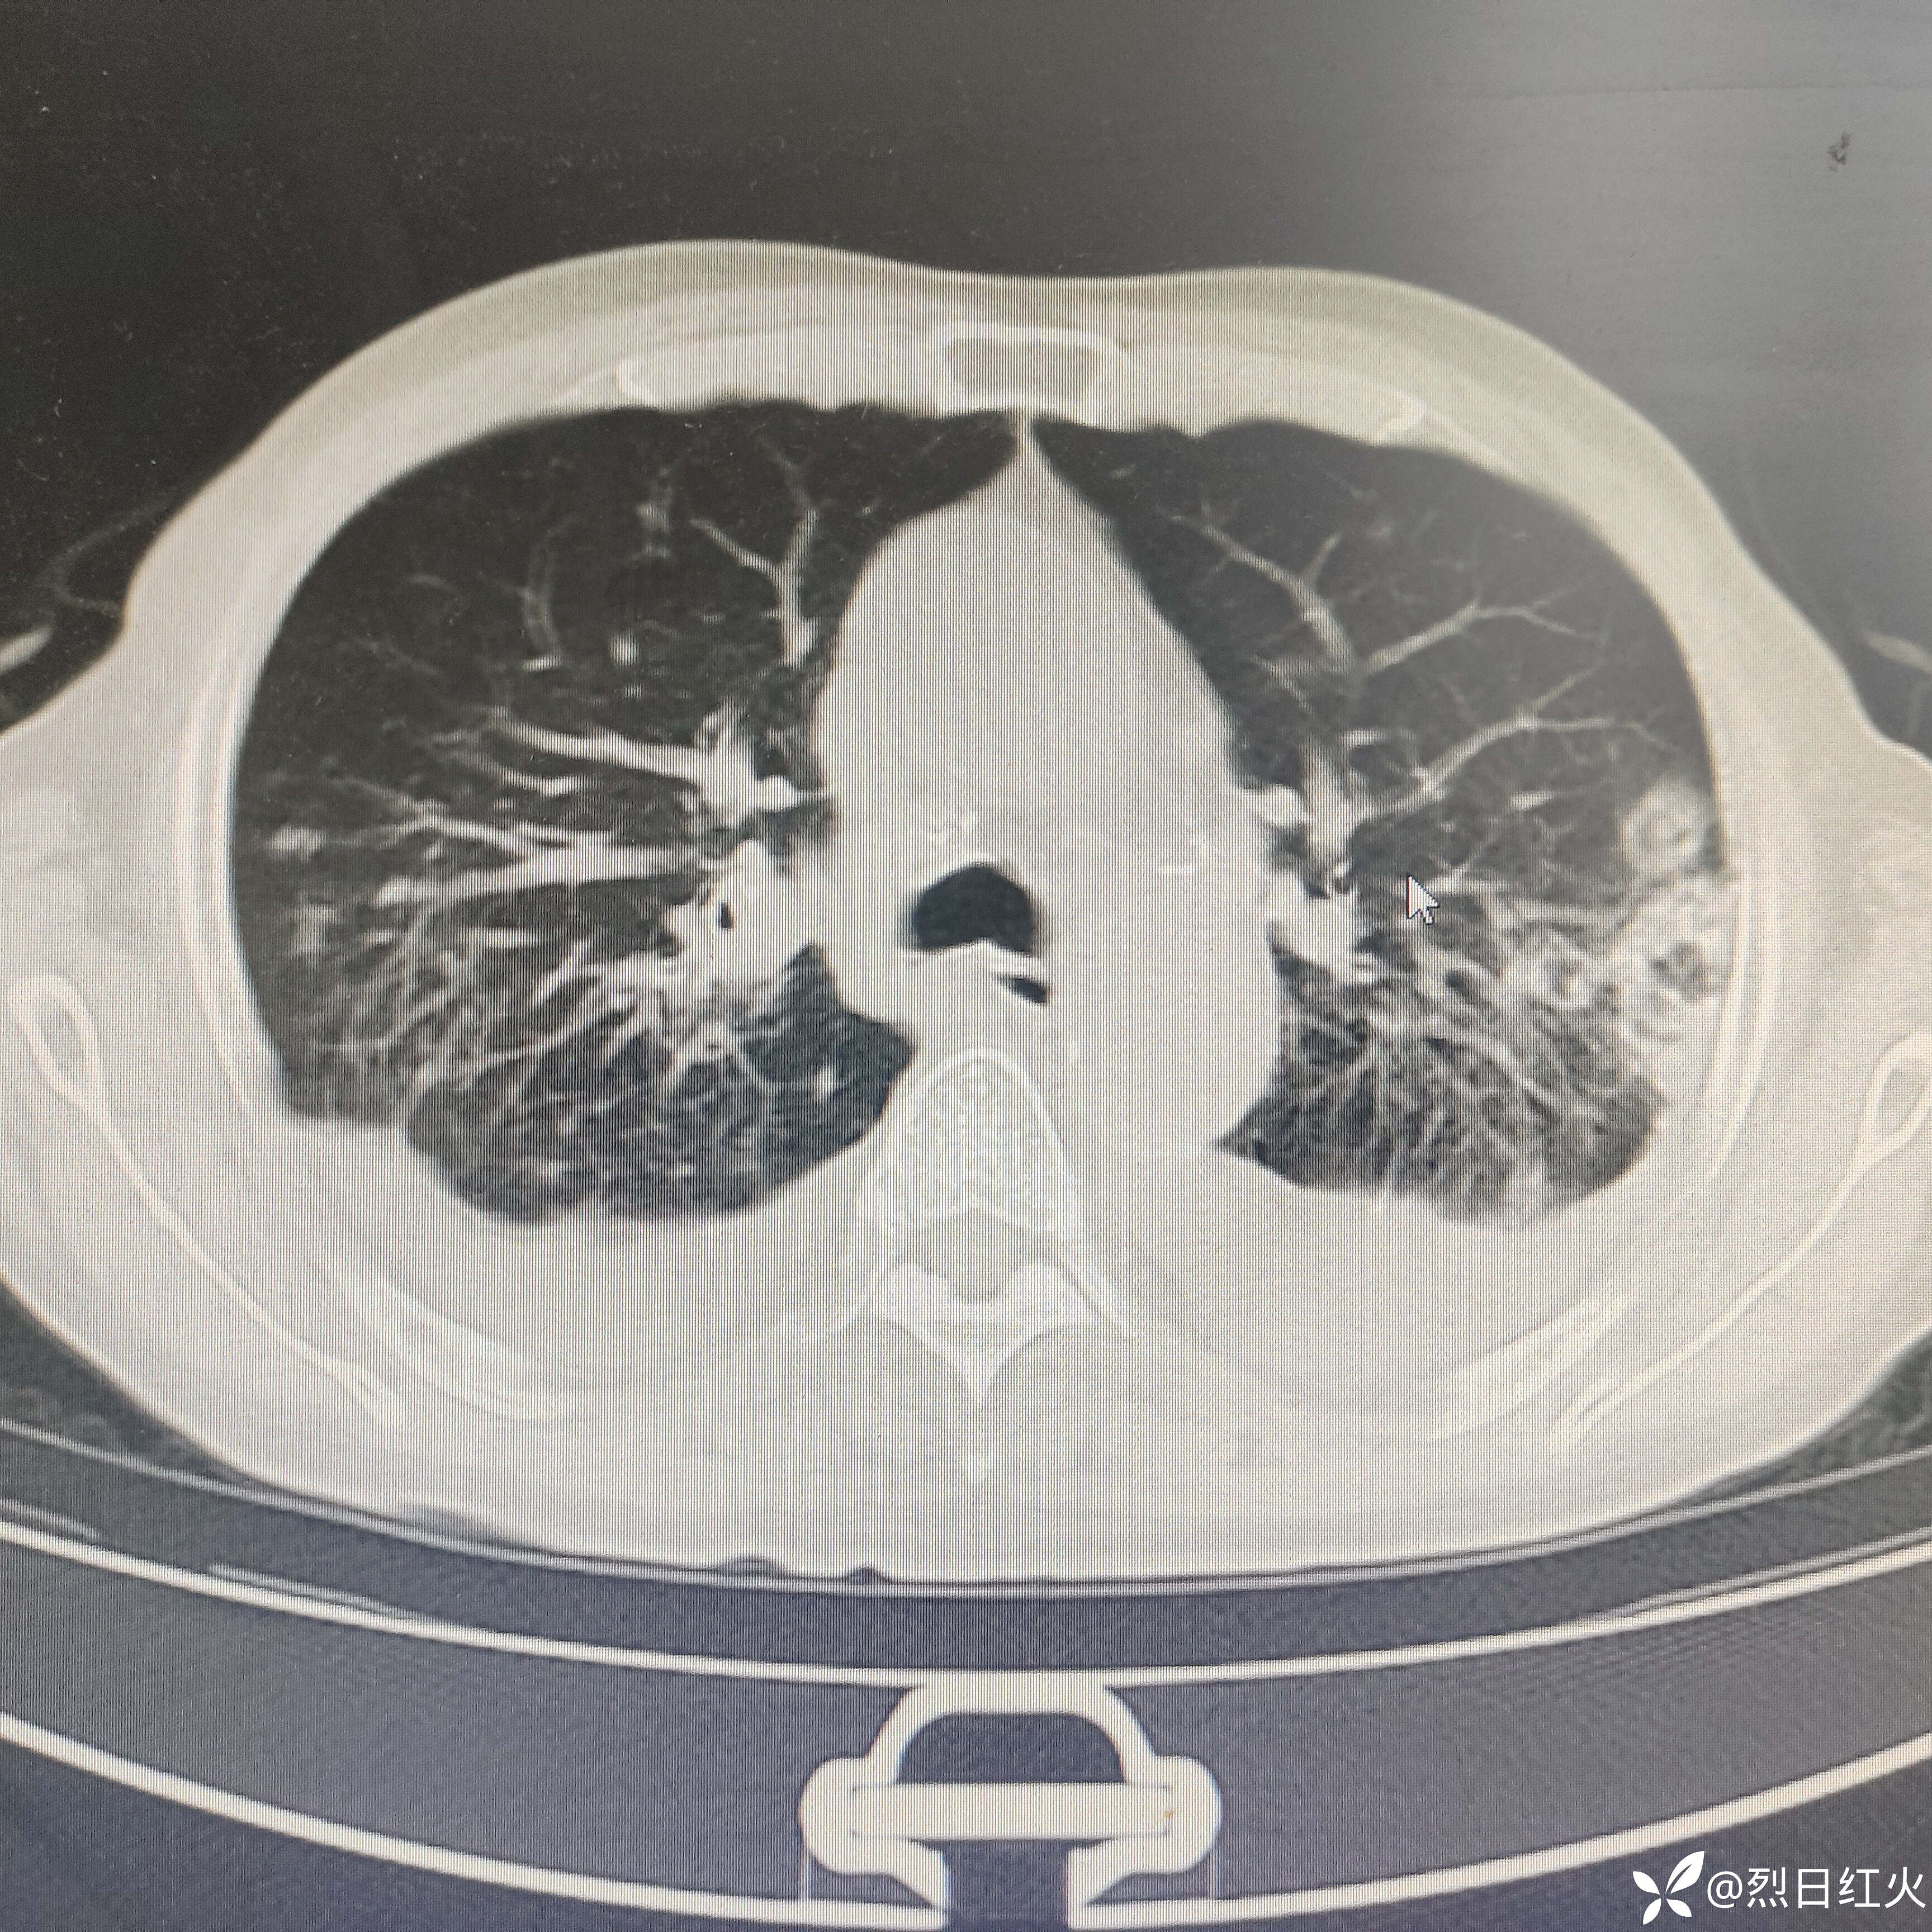

5辅助检查:心电图:窦性心律,中度ST压低(Ⅱ,aVF,V6),T波异常(可能是下壁心肌缺血)(Ⅱ,aVF)。心脏彩超:主动脉瓣退行性改变伴关闭不全(轻度),三尖瓣关闭不全(中-重度)、肺动脉高压(轻度),左室舒张功能减退,左室收缩功能正常。腹部彩超:肝脏囊肿,左肾囊肿。胸部CT:1、右肺中叶、下叶及左肺感染性病变。2、慢性支气管炎、肺气肿。3、双肺改变,请结合其职业史,建议进一步检查,除外尘肺。4、双侧胸膜局限性增厚。

患者血象较入院前升高,胸部CT影像感染灶明显加重。右肺上叶见晕征,空洞完善G实验,GM实验,NGS相关检查。

CT平扫:双侧胸廓对称,双肺纹理增多、紊乱,肺野透光度增强,双肺见多发小结节样及条索状稍高密度影,边界清楚,双肺呈对称性分布,以双肺上叶中内带为著,双肺见多发斑片状稍高密度影,边界欠清,纵隔气管居中,纵隔内未见明显肿大淋巴结影,心影未见明显增大,心包未见明显增厚,双侧胸腔见弧形稍低密度影,胸壁软组织未见明显异常,扫描范围内:肝内见多发圆形低密度影,CT值约6HU,较大直径约2.8cm。

1、右肺中叶、下叶及左肺感染性病变治疗后复查,与2024年3月20日CT对比,病灶有所增加。

2、慢性支气管炎、肺气肿。

3、双肺改变,请结合其职业史,建议进一步检查,除外尘肺。

4、双侧胸腔积液。